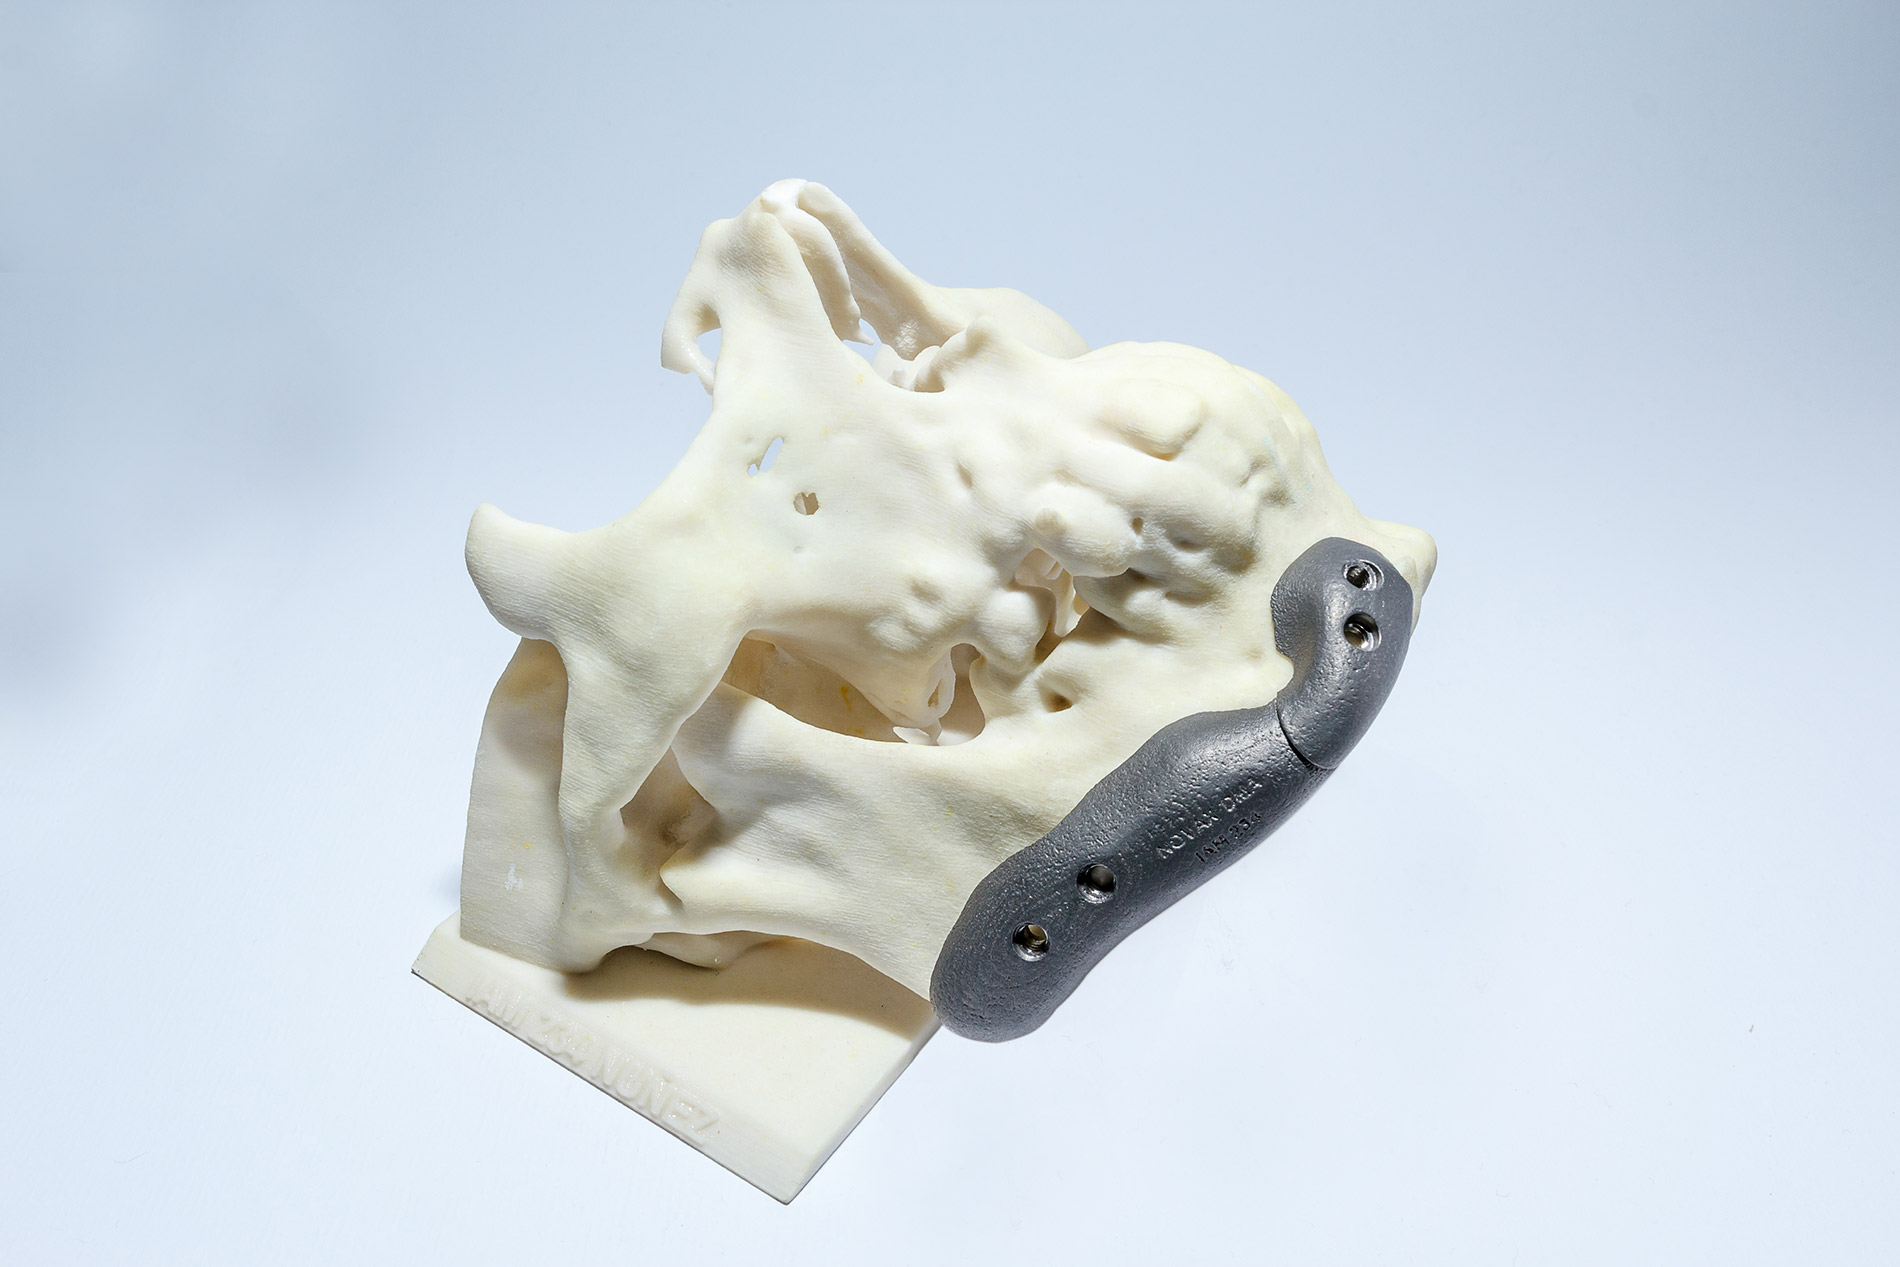

El prototipo plástico se consigue a partir de la realización de un modelado digital 3D. La pieza obtenida respeta las medidas de la anatomía, pudiendo el cirujano, de esta manera, tener una idea real de la patología a tratar.

Una vez obtenida la información de la TAC o MRI y modelado el 3D digital, podemos modelar la prótesis que se necesita (por ejemplo, una porción de calota faltante) y posteriormente realizarla en resina plástica. De esta manera validamos la adaptación del futuro implante a la anatomía. El cirujano puede verificar las imágenes modeladas digitalmente o el prototipo en resina plástica, y sugerir modificaciones dando paso al proceso final.

En otros casos el cirujano puede solicitar el modelado de alguna región anatómica con la finalidad de hacer una planificación prequirúrgica, por ejemplo, realizar en su consulta un moldeado muy exigente de placas maxilares. Luego de recibir el modelo anatómico o prototipo en resina, modela las placas que va a utilizar y las devuelve a la empresa para que sean esterilizadas antes de ser usadas, reduciendo considerablemente el tiempo quirúrgico.

2 | Permite la reconstrucción de modelos en tres dimensiones y a tamaño real para lograr un mejor ajuste anatómico.

6 | Se aplica a diferentes regiones anatómicas: cráneo, ATM pelvis, etc.